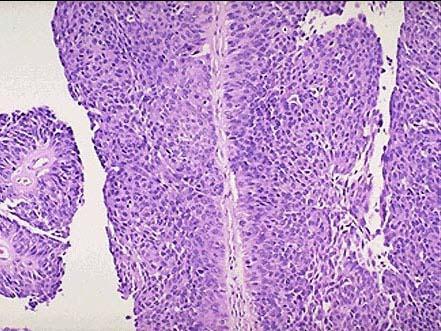

问题 患者,男,55岁,因无痛性肉眼血尿就诊,膀胱镜见膀胱侧壁有一直径3cm的肿块,暗红色,表面有溃疡。活检如下图所示,确切的诊断是 ( )

选项 A.膀胱结核 B.膀胱慢性炎 C.膀胱移行细胞乳头状瘤 D.膀胱移行细胞癌 E.以上都不是

答案 D